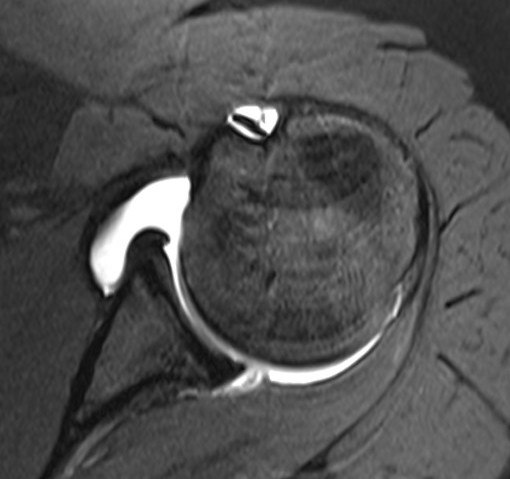

Anterior instability but no anterior labral tear on MRI

Intact labrum on MRI

Anterior labrum intact, evidence of capsule tearing + HAGL on MRI